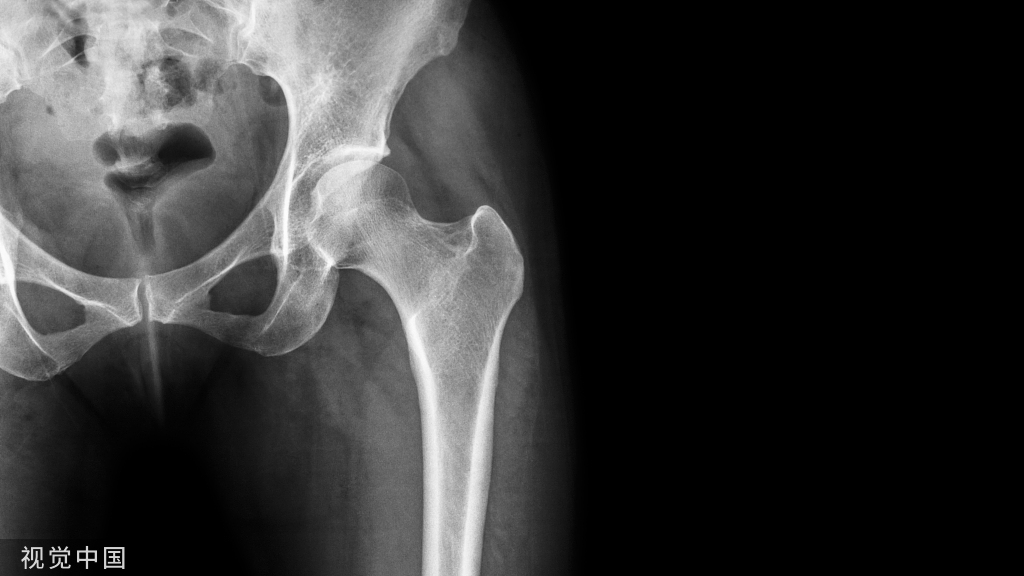

骨质疏松症是一种使骨骼变得脆弱的疾病。这大大增加了骨折的风险,即使是轻微的跌倒或撞击。据我国2018年的流行病学调查显示,50岁以上人群女性患病率为32.1%,男性为6.0%;而65岁以上人群骨质疏松女性患病率为51.6%,男性为10.7%。

骨质疏松症( osteoporosis,OP) 是最常见的骨骼疾病,是一种以骨量低,骨组织微结构损坏,导致骨脆性增加,易发生骨折为特征的全身性骨病。

骨质疏松性骨折,多见于老年女性,特别会发生在腰椎及胸椎,即出现锥体压缩性骨折,这是老年性骨质疏松症最常见和最严重的并发症。